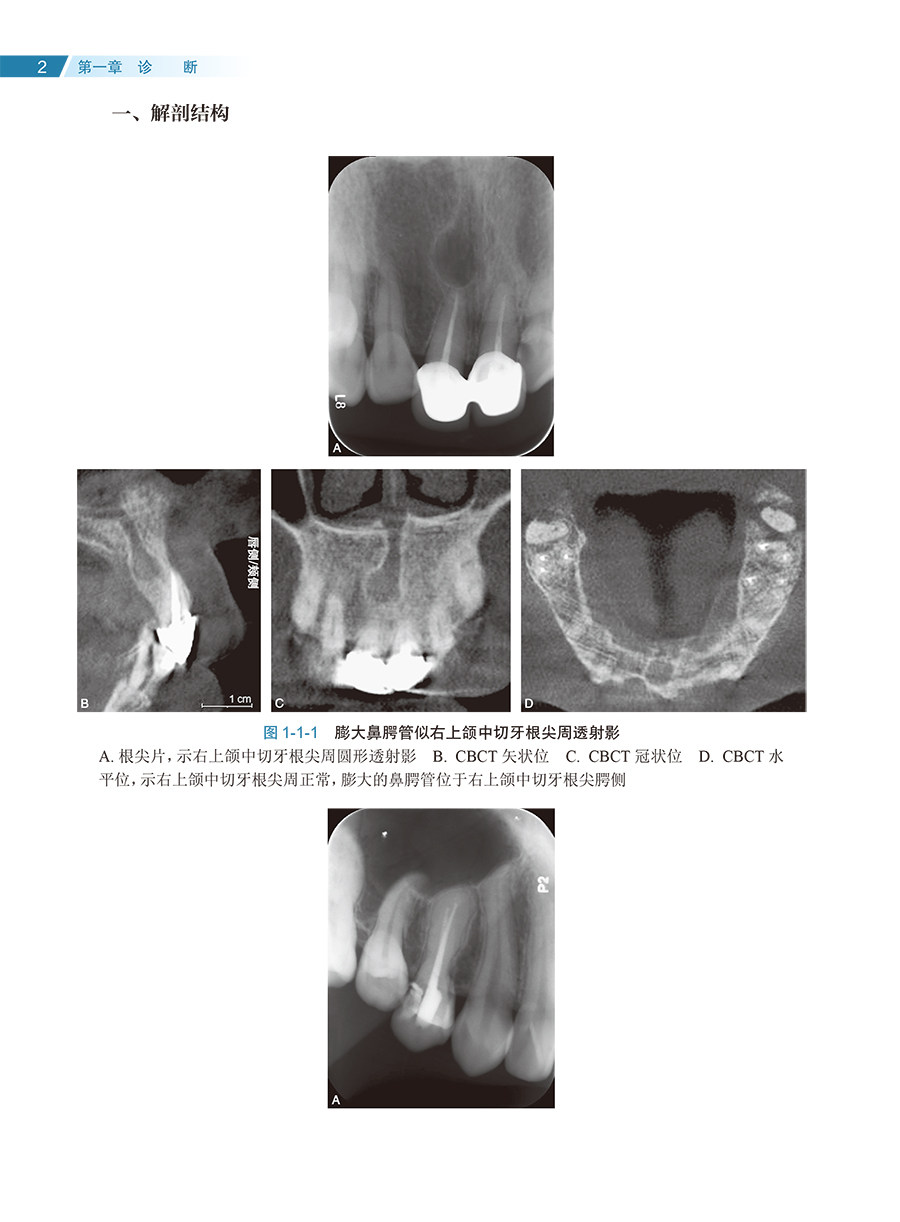

社口腔科学 根尖周透射影根裂诊断鉴别非手术治疗显微根尖外科再植术牙髓病人民卫生出版 显微根管外科疑难病例解析彩色图谱 王捍国